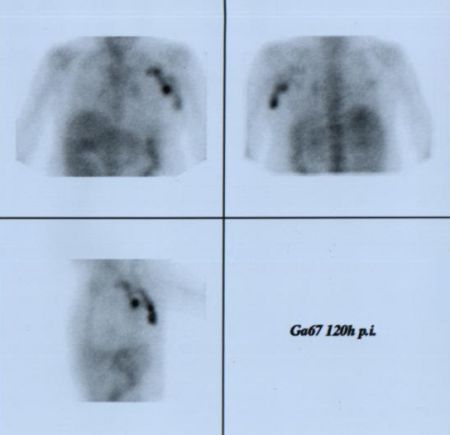

Projekce

120 hodin p.i.:

obr.5): planární AP, PA,

levá boční:

obr.6): celotělové A/P a

P/A: